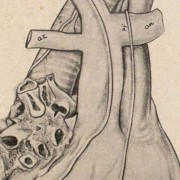

Lilly Ebstein Lowenstein (1897-1966) led a life between science and art, drawing and taking photographs in the fields of Medicine and Zoology. In her work, Lilly combined her technical knowledge of photography and drawing, the study of the sciences and a remarkable talent for aesthetics. She was born in Germany and studied at the Lette-Verein School in Berlin from 1911 to 1914. In 1925, she immigrated with her husband and two children to São Paulo. In 1926, she became an illustrator and photomicrographer at the Illustration and Photography Department at the School of Medicine (USP, as of 1934), which she headed for thirty years after 1932. Lilly collaborated at Instituto Biológico de Defesa Agrícola e Animal (the Biological Institute for the Defense of Agriculture and Animals), from 1930 to 1935, namely in the Avian Pathology Department. A life with art dedicated to the research and dissemination of science.